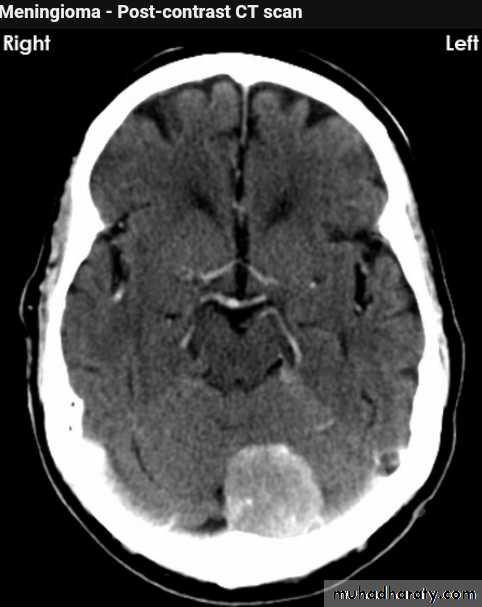

Meningioma

Benign tumor arise from the arachnid cells of the meningeal covering of the brain are most common primary intracranial neoplasm

Usually present in middle age female

it is well defined extra axial , located mainly at the convexity of the skull periphery

rounded or sessile , plaque like , specially the tumor arise from the cribriform plate , or those arise from the petrus bone , planum spheniodale , or from skeleton of the pituitary fosse .

CT finding

meningioma presented as isodense area or slightly hyper density area with surrounded crescent of hypo density ( csf cap ) post contrast injection the lesion enhance homogeneously with enhancing Dural tail .

20 % show calcification

hyperostosis & thickening of the near by bony part of the skull & diplioc space .

it may be associated with little or no peri focal edema .